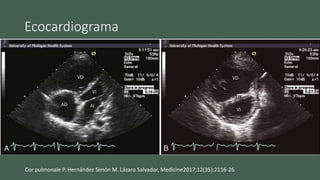

Ecocardiograma

• Aumento el grosor parietal del VD

• Movimiento paradójico del septo hacia ventrículo izquierdo

• Crecimiento el VD

• Detectar la etiología

Cor pulmonale P. Hernández Simón M. Lázaro Salvador, Medicine2017;12(35):2116-26